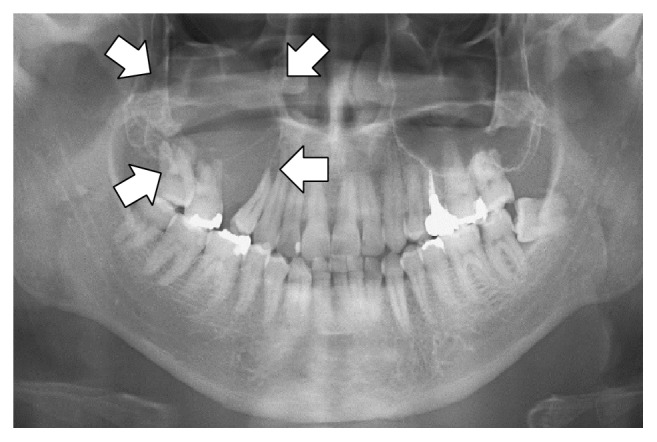

## 视觉微调

用于微调视觉或多模态模型的数据集还包括图像输入。例如, [Llama 3.2 视觉笔记本](https://colab.research.google.com/github/unslothai/notebooks/blob/main/nb/Llama3.2_\(11B\)-Vision.ipynb#scrollTo=vITh0KVJ10qX) 使用放射影像案例展示 AI 如何帮助医学专业人员更高效地分析 X 光、CT 扫描和超声图像。

我们将使用采样的 ROCO 放射影像数据集。你可以访问该数据集 [此处](https://www.google.com/url?q=https%3A%2F%2Fhuggingface.co%2Fdatasets%2Funsloth%2FRadiology_mini)。该数据集包括展示医学病症和疾病的 X 光、CT 扫描和超声图像。每张图像都有专家撰写的说明性标题。目标是微调一个视觉语言模型(VLM),使其成为对医学专业人员有用的分析工具。

让我们查看数据集,并检查第一个示例显示的内容:

用于微调视觉或多模态模型的数据集还包括图像输入。例如, [Llama 3.2 视觉笔记本](https://colab.research.google.com/github/unslothai/notebooks/blob/main/nb/Llama3.2_\(11B\)-Vision.ipynb#scrollTo=vITh0KVJ10qX) 使用放射影像案例展示 AI 如何帮助医学专业人员更高效地分析 X 光、CT 扫描和超声图像。

我们将使用采样的 ROCO 放射影像数据集。你可以访问该数据集 [此处](https://www.google.com/url?q=https%3A%2F%2Fhuggingface.co%2Fdatasets%2Funsloth%2FRadiology_mini)。该数据集包括展示医学病症和疾病的 X 光、CT 扫描和超声图像。每张图像都有专家撰写的说明性标题。目标是微调一个视觉语言模型(VLM),使其成为对医学专业人员有用的分析工具。

让我们查看数据集,并检查第一个示例显示的内容:

|  | 全景放射影像显示右后上颌出现溶骨性病变,并伴随上颌窦底的吸收(箭头所示)。 |

在进行任何微调之前,也许视觉模型已经知道如何分析这些图像?让我们检查是否如此!

结果为:

```

该放射影像似乎是上下牙列的全景图像,具体为全口断层摄影(Orthopantomogram,OPG)。

* 该全景放射影像显示正常的牙齿结构。

* 右上方有一处异常区,表现为放射性透亮的骨质区域,对应于鼻窦(antrum)。

**主要观察**

* 左上牙之间的骨质相对放射性致密。

* 图像上方有两个大箭头,提示需要对该区域进行更仔细的检查。其中一个箭头位于左侧,另一个位于右侧。然而,仅有

```